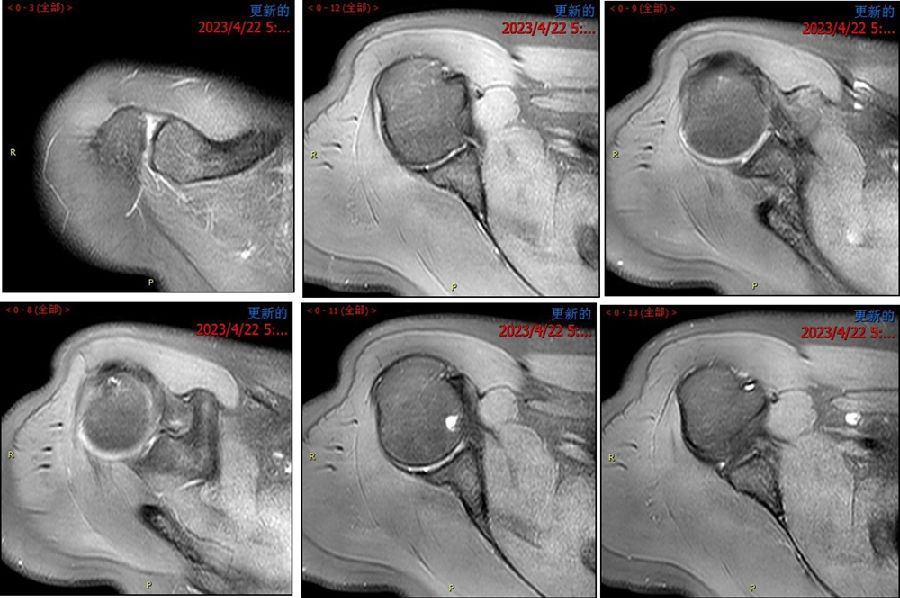

图39 此次复发脱位MR评估

图40 影像学评估

双侧CT三维扫描显示:D=34mm,d=3mm,d/D=肩胛盂骨缺损9%;GT=25.2mm,HIS=30mm。

该患者为轨迹外Hill-Sachs损伤,需要做bankart修补,同时轨迹外做remplissage手术。